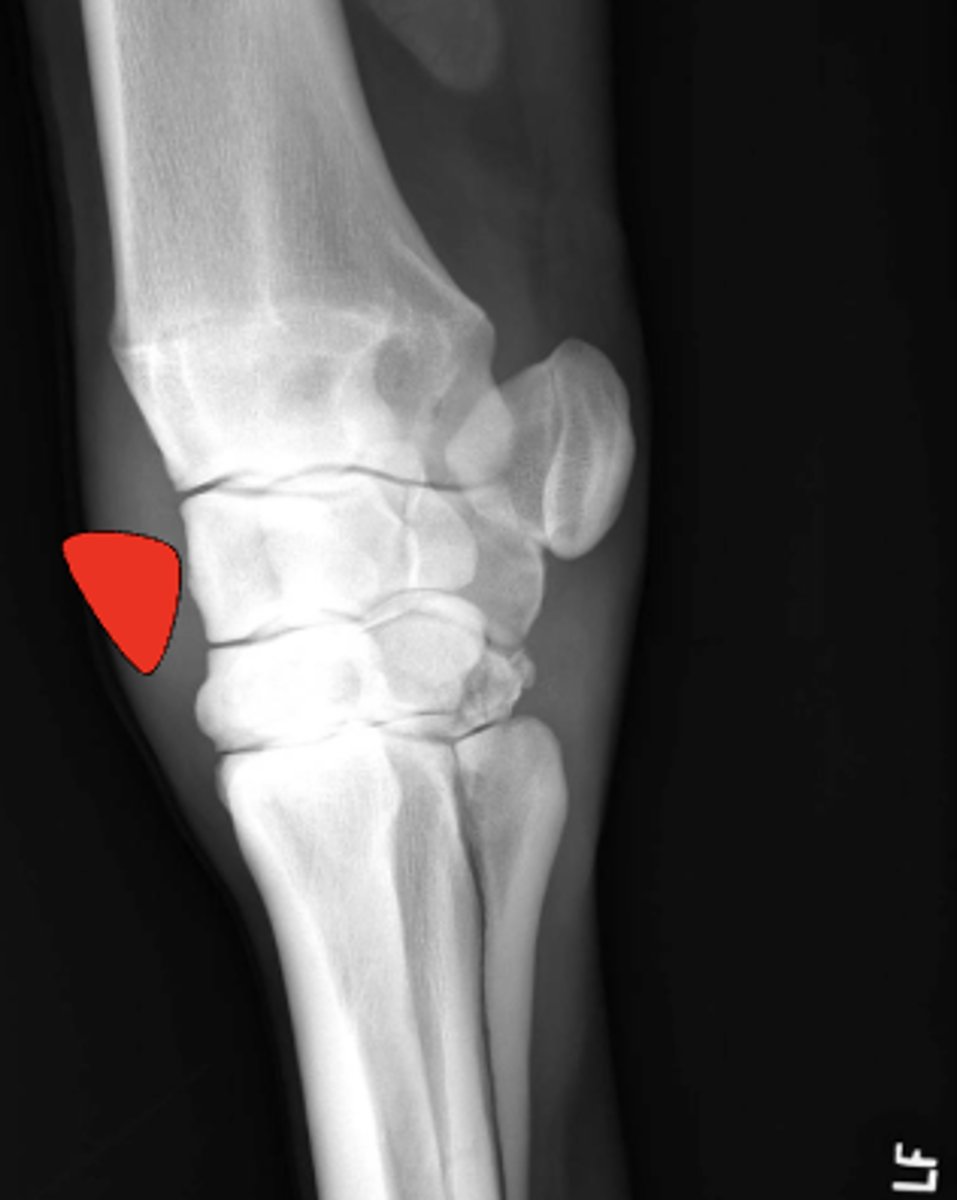

Where is this fragment located?

Type III

What fracture type is this?

Which Salter-Harris fracture is pictured?